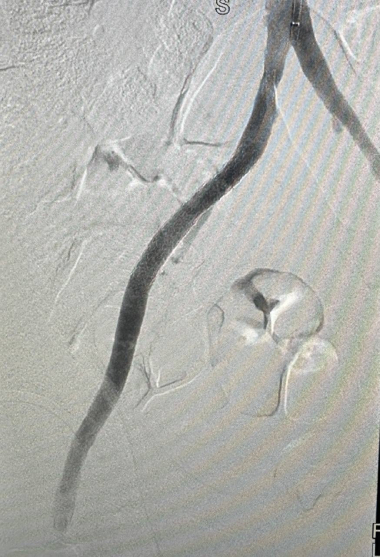

К нам поступила пациентка 64-х лет с хронической ишемией нижних конечностей с проявлениями перемежающейся хромоты. В ходе обследования мы выявили критические стенозы обеих внутренних сонных артерий, декомпенсированный сахарный диабет, контрастиндуцированную нефропатию.

Коморбидной пациентке с мультифокальным атеросклерозом, тяжёлым проксимальным критическим стенозом передней нисходящей артерии до 90%, умеренным аортальным стенозом, критическим стенозом правой сонной артерии 85%, левой сонной 80% решили провести этапную реваскуляризацию магистральных артерий.

Для снижения риска периоперационных осложнений специалисты отделения сердечно-сосудистой хирургии использовали этапные эндоваскулярные методики.

На первом этапе (05.09.2024) женщине выполнили стентирование внутренней сонной артерии слева. Во время госпитализации на втором этапе для стентирования ВСА у пациентки был диагностирован острый Q-не образующий инфаркт миокарда передней локализации с гемодинамически значимым поражением устья передней межжелудочковой ветви (ПМЖВ).

Врачи приняли решение направить пациентку на стентирование ПМЖВ левой коронарной артерии.

Третьим этапом (22.10.2024) было выполнено стентирование правой внутренней сонной артерии. При контрольном ДС зона реконструкции была проходима.

После лечения самочувствие пациентки значительно улучшилось.